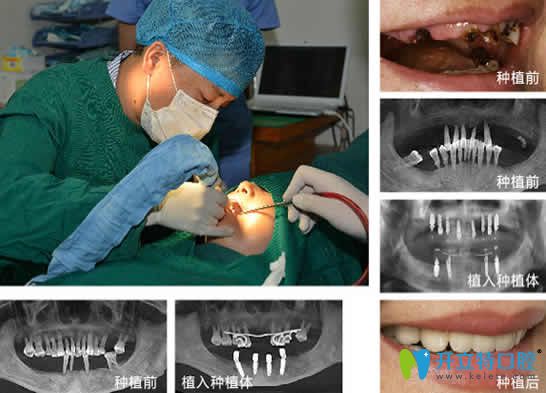

全庆波,第四口腔种植专业硕士毕业,现任口腔种植科主任。从事种植牙专业10余年,多次在国内外口腔进修学习种植牙新技术。10年前他从第四毕业后是留校工作,可谓前程似锦,但是在一次德国访问的经历,让他对德国种植牙3D打印、4D导航技术的痴迷,使全医生毅然决然辞去公立的“铁饭碗”而加入了民营口腔。全庆波医生对种植牙有着很深的造诣,至今已成功完成各种种植牙案例10000余颗。

擅长项目:全口牙种植、半口牙种植、即刻种植牙、微创种植牙等。

口腔全庆波医生种植牙案例效果及顾客评论:

全医生掌握了“4D”种植牙核心技术,种植牙整体水平的很高,整个手术过程中无痛,种植后效果也很好。